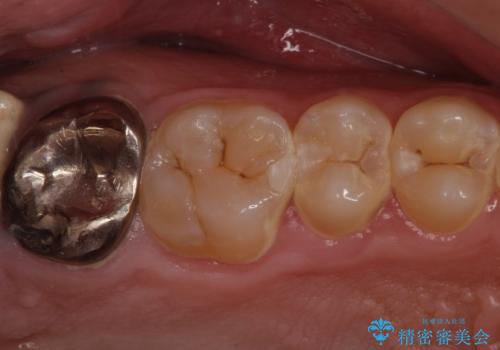

- 口の中を予算の範囲内でできるだけきれいにしたいとのことで来院された患者様です。

矯正治療と虫歯治療を組み合わせてご提案しましたが、ご予算との兼ね合いで虫歯治療のみを行うこととなりました。

奥歯は十分な歯の高さがなかったため、クラウンをかぶせる前に歯周外科治療で歯の高さを出しています。